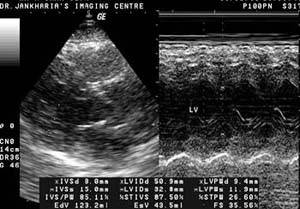

2D

Echo – Two Dimensional Echocardiography |

Q4. What happens after the procedure?

A. Although the Cardiologist who

is performing this test may explain what is being

seen on the screen as the examination is in progress,

it is essential to obtain precise measurements from

the paper and videotape recordings. If you have had

previous echocardiograms, the new ones will be compared

with those and the cardiologist will analyze any differences.

Your doctor will review with you the results and

final diagnosis.